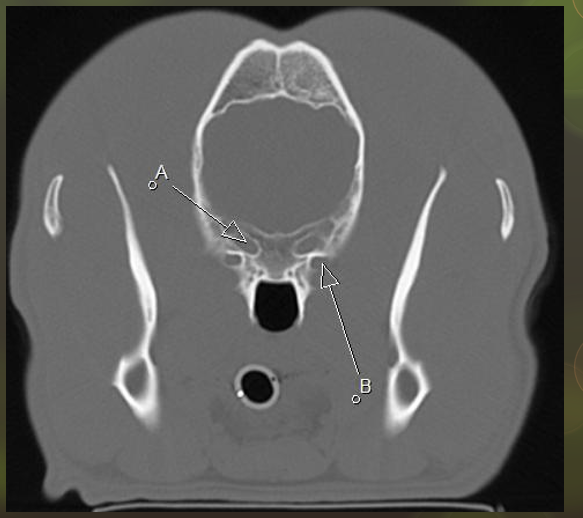

A orbital fissure

B rostral alar foramen leading to alar canal, round foramen inside the skull